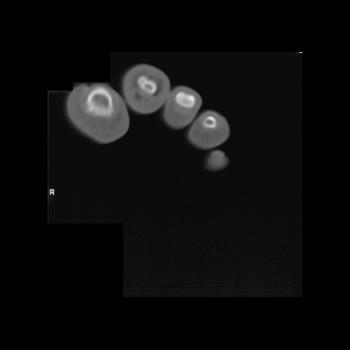

The regions of the foot that are most prone to neuropathic arthropathy include the forefoot, the metatarsal-phalangeal joints, the tarsal-metatarsal joints and intertarsal joints.

Neuropathic osteoarthropathy begins with an acute, resorptive, hyperemic phase. On imaging studies, the bone abnormalities are similar in appearance to infection. The forefoot is involved most commonly, followed by the midfoot. The metatarsal-phalangeal joint regions may demonstrate osteolysis.

The sclerotic or hypertrophic stage follows. Bone abnormalities include sclerosis, erosions, fractures with fragmentation, joint dissolution and subluxation or dislocation resulting in malalignment (Figure here: Charcot Joint).